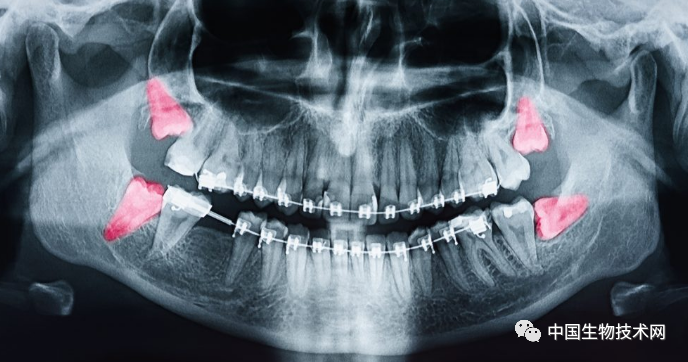

在人類近親中,只有黑猩猩像我們一樣會延長在關鍵發育期的時間。但即使是黑猩猩,也早早長齊了滿口牙。而現代智人直到青春期結束才開始萌出第三磨牙,即阻生智齒(俗稱智齒)。健康的智齒可以幫助咀嚼,但有問題的智齒可能會引起牙齦組織發炎和感染,最終導致冠周炎。所以,很多人不得不拔掉有問題的智齒。

我們用來把食物磨成糊狀的成熟牙齒通常分三個階段從口腔中萌出,即6歲、12歲和18歲左右。

其他靈長類動物的成年臼齒長得更早。像人類的近親黑猩猩(Pan troglodytes)在3歲、6歲和12歲時都會長出臼齒。黃狒狒(Papio cynocephalus)在7歲時有了最後一顆成年臼齒;而恆河猴(Macaca mulatta)在6歲時就已經長出全部牙齒。

限制牙齒萌出時間的一個重要因素是空間。如果下頜不夠大,就無法放下全套的成年牙齒,那麼也就沒必要把它們全都塞進去。

早期人類的口腔空間並不像現在這樣大,阻生智齒(俗稱智齒)是我們人類面臨的一個主要問題。但這並不能解釋為什麼它們在我們的生命中出現得這麼晚,或者為什麼後面的那些智齒似乎總在製造麻煩。